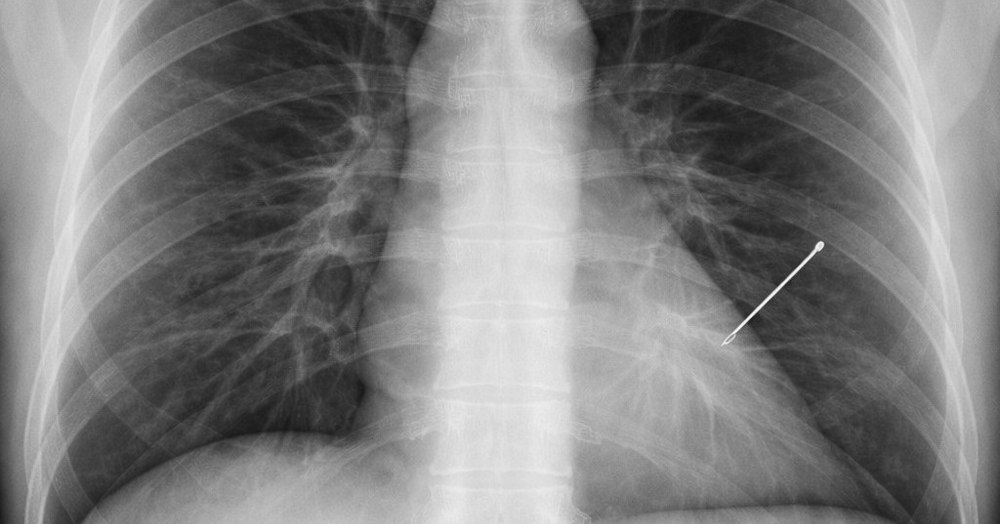

Un caz medical neobișnuit a fost descoperit întâmplător la o femeie de aproximativ 55 de ani, în timpul unui control de rutină: o radiografie a arătat prezența unui ac de cusut în plămânul stâng, care ar fi rămas în organism, timp de aproape 30 de ani.

Caz uluitor. O femeie a trăit 30 de ani cu un ac în plămân fără să știe. Descoperirea care l-a șocat pe un reputat medic: „Am înghețat”